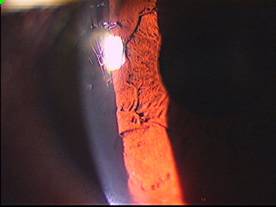

传统裂隙灯生物显微镜最初的检查功能只能通过目镜一人观察,且病历图像无法进行留底,已经不能满足现代临床医学发展的需要,特别是在多人示教上形成难以突破的障碍。计算机数字技术在医学领域的应用为裂隙灯的数字化发展提供了解决方案,与电脑结合加上数字软件分析系统的数字化裂隙灯已被国内大型医院及科研教学单位所采用,并且已逐步向中小医院普及。对传统裂隙灯的数字化改造,是在传统裂隙灯生物显微镜上加装相匹配的光路转换镜头,获得高清晰度数码图像。从而实现了仪器设备的升级换代,改变了仪器老化的壮况,提高了仪器的完好率,更大程度上节省了医院的采购经费。光学转换镜头由温州医学院眼视光学院著名光学教授金成鹏组织开发,镜头均采用德国技术制作加工,防潮湿、防霉镀膜处理,能保证长久良好的光学效果。

数字软件分析系统实现了电脑观察辅助诊断的功能,为临床提供客观和量化的诊断依据,尤其在科研、教学的应用中有了更完善的平台。